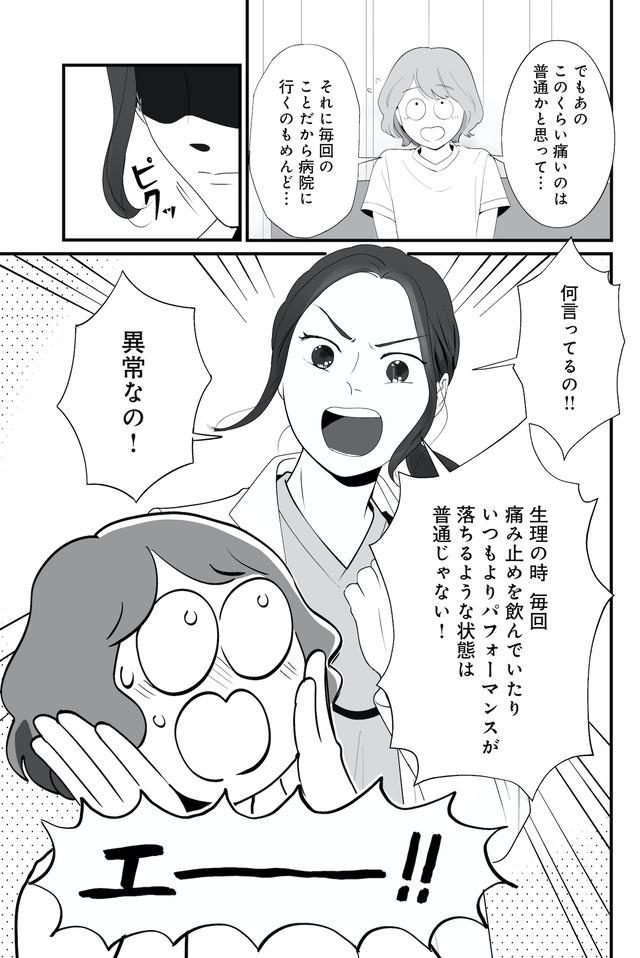

生理痛やPMSに苦しむあかり。通勤中、貧血で倒れて病院に運ばれたことをきっかけに、自分にあった生理用品や治療法を教えてもらうことに。

生理、吸水ショーツ、月経カップ、ミレーナ、ピル、卵子凍結、性のこと…

知ると知らないで大きく変わる! 自分のカラダとの向き合い方とは?